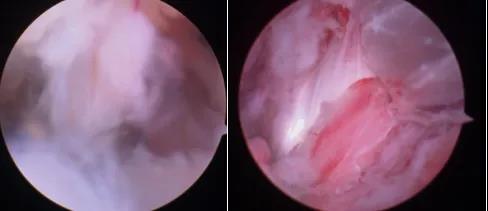

关节镜下探查距腓前韧带撕裂伴松弛,关节镜下自体肌腱重建损伤韧带,张力良好